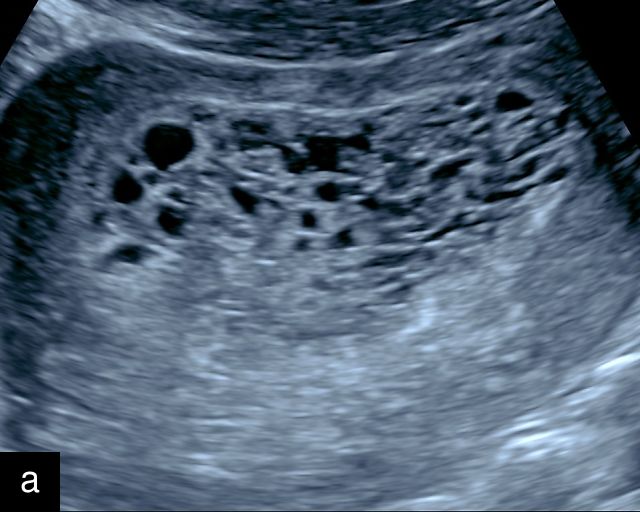

Placental mesenchymal dysplasia

Placental mesenchymal dysplasia (PMD) was first described by Moscoso et al. in 1991.167 It is an uncommon placental vascular abnormality characterized by mesenchymal stem villous hyperplasia, edema and cystic dilation.9,105,168 PMD complicates approximately 1 in 500 pregnancies (0.2%) and is often associated with placental mosaicism.9 There is a 3.6 : 1 female: male preponderance. Maternal serum alpha-fetoprotein (AFP) levels may also be markedly elevated in these pregnancies.169 Despite its clinical significance, PMD is underreported, and many sonographers, obstetricians and pathologists are unfamiliar with the condition, often confusing it with a hydatidiform mole.106,153,170,171,172

PMD is strongly associated with adverse pregnancy outcomes, including pre-eclampsia, FGR and fetal demise.106,173 It has also been found in association with Beckwith–Wiedemann syndrome and various congenital anomalies, including skeletal dysplasias and CHARGE syndrome.106,174,175,176 A systematic review by Nayeri et al. reported that only 9% of pregnancies with PMD resulted in a normal outcome for the baby106.

On ultrasound, PMD appears as a thickened placenta with multiple small cysts of varying size, creating a 'snowstorm' appearance that closely resembles a hydatidiform molar pregnancy (Figure 14; Video 8).9,105,106,169,172 Differentiating PMD from a molar pregnancy can be challenging, particularly in twin pregnancies in which a normal twin coexists with a cotwin that has an enlarged, cystic placenta.169 In complete molar pregnancy, the uterus is entirely filled with cystic tissue, showing a snowstorm appearance without identifiable fetal structures. Partial molar pregnancies, on the other hand, typically feature an enlarged cystic placenta coexisting with an abnormal fetus.105

14

(a–e) Grayscale ultrasound of placental mesenchymal dysplasia showing thickened placentas with multiple round cysts of varying size.